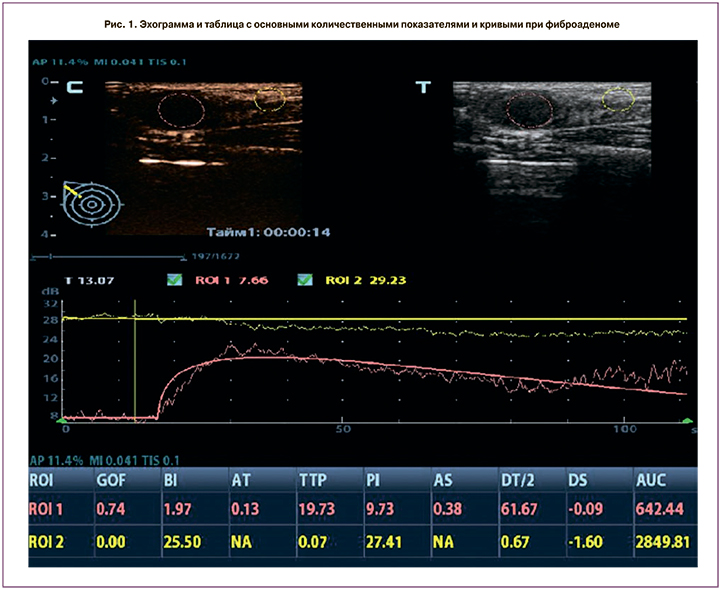

При оценке качественных характеристик КУУЗИ в 65,8% злокачественных и в 25% доброкачественных узловых образованиях размеры опухоли оказались больше, чем в В-режиме, поэтому для получения количественных характеристик контрастирования окружающих тканей вторая зона интереса (ROI 2 диаметром 4–7 мм) была в перитуморальной паренхиме на расстоянии 5–9 мм от края узлового образования. При соблюдении вышеописанных условий проведения исследования анализ полученных кривых производился автоматически и отображался на экране в виде таблиц (рис. 1–2).

- соответствие (Goodness of Fit, GOF): расчет степени соответствия кривой; диапазон 0–1, где 1 означает, что кривая точно соответствует исходным данным;

- интенсивность фона (Base Intensity, BI): фоновая интенсивность в отсутствие контрастного вещества;

- время появления контрастного усиления (Arrival Time, АТ, с) – момент времени, когда начинает расти интенсивность контрастного усиления;

- наклон при подъеме (Ascending Slope, AS, дБ/с) – скорость нарастания интенсивности контрастного усиления, наклон на участке между начальной точкой перфузии и максимумом;

- время максимума (Time to Peak, TTP, с) – момент времени, когда интенсивность контрастного усиления достигает максимального значения.

- максимум интенсивности (Peak Intensity, PI, дБ) – максимальная интенсивность контрастного усиления;

- время полувыведения (DT/2, с) – время, за которое интенсивность контрастного усиления снижается до половины максимального значения;

- скорость снижения контрастного усиления (Descending Slope, DS, дБ/с) – скорость снижения интенсивности контрастного усиления, наклон кривой при снижении интенсивности контрастного усиления;

- площадь под кривой (Area under the curve, AUC, дБ/с) – площадь под кривой «время–интенсивность».